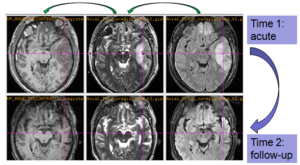

Experiments: Registration of longitudinal data

The NA-MIC DBP project on TBI analysis (UCLA partner) includes serial multi-modal MRI at acute phase and follow-up after six months. We test mutual-information-based linear registration of multi-modal MRI data within each time point and nonlinear registration (b-spline) of follow-up scans to obtain sets of images mapped into the same coordinate system. Preliminary results demonstrate the large deformations due to mass effect of a large lesion but also significant large regional changes of multi-modal MRI contrast from actute to follow-up.

Longitudinal co-registration of multi-modal MRI.

Segmented white matter and temporal lobe (yellow) at acute phase and after 6 month follow-up.